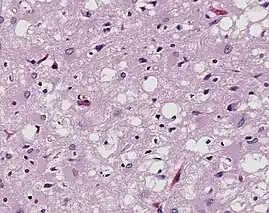

Prions are misfolded proteins that are transmissible and can influence abnormal folding of normal proteins in the brain. They do not contain any DNA or RNA and cannot replicate other than to convert already existing normal proteins to the misfolded state. These abnormally folded proteins are found characteristically in many neurodegenerative diseases as they aggregate the central nervous system and create plaques that damages the tissue structure. This essentially creates "holes" in the tissue. It has been found that prions transmit three ways: obtained, familial, and sporadic. It has also been found that plants play the role of vector for prions. There are eight different diseases that affect mammals that are caused by prions such as scrapie, bovine spongiform encephalopathy (mad cow disease) and feline spongiform encephalopathy (FSE). There are also ten diseases that affect humans, such as Creutzfeldt–Jakob disease (CJD)[20] and Fatal familial insomnia (FFI).